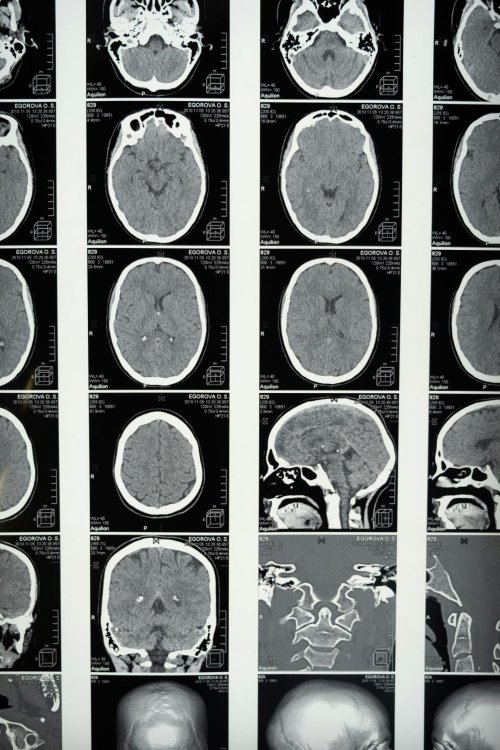

那么,缺血性脑血栓到底是怎么回事?简单来说,就是我们身体里的血管负责输送营养和氧气到各个器官,包括大脑。当大脑里的血管因为某些原因被堵塞后,血液就无法正常流通,大脑相应的区域就会因为得不到足够的营养和氧气而受到影响,这就发生了缺血性脑血栓。而恢复的过程,很大程度上就是让堵塞的血管尽可能通畅,让血液重新顺畅地流到大脑需要的地方,同时帮助受损的身体机能慢慢恢复。

“血脉通畅”为什么对恢复速度影响这么大呢?其实也不难理解,身体的各个组织和器官,包括大脑,都离不开血液带来的营养和氧气。当血管堵塞后,大脑的部分区域就像断了水和粮的地方,功能会受到影响。而治疗的关键就是尽快打通堵塞的血管,或者让血液能够通过其他途径到达受损区域。如果血脉能够保持相对通畅的状态,大脑就能及时获得修复所需要的“原材料”,身体的各项机能也能更快地得到恢复。相反,如果血脉通畅程度不够,大脑得不到充足的营养供应,恢复自然就会慢一些。